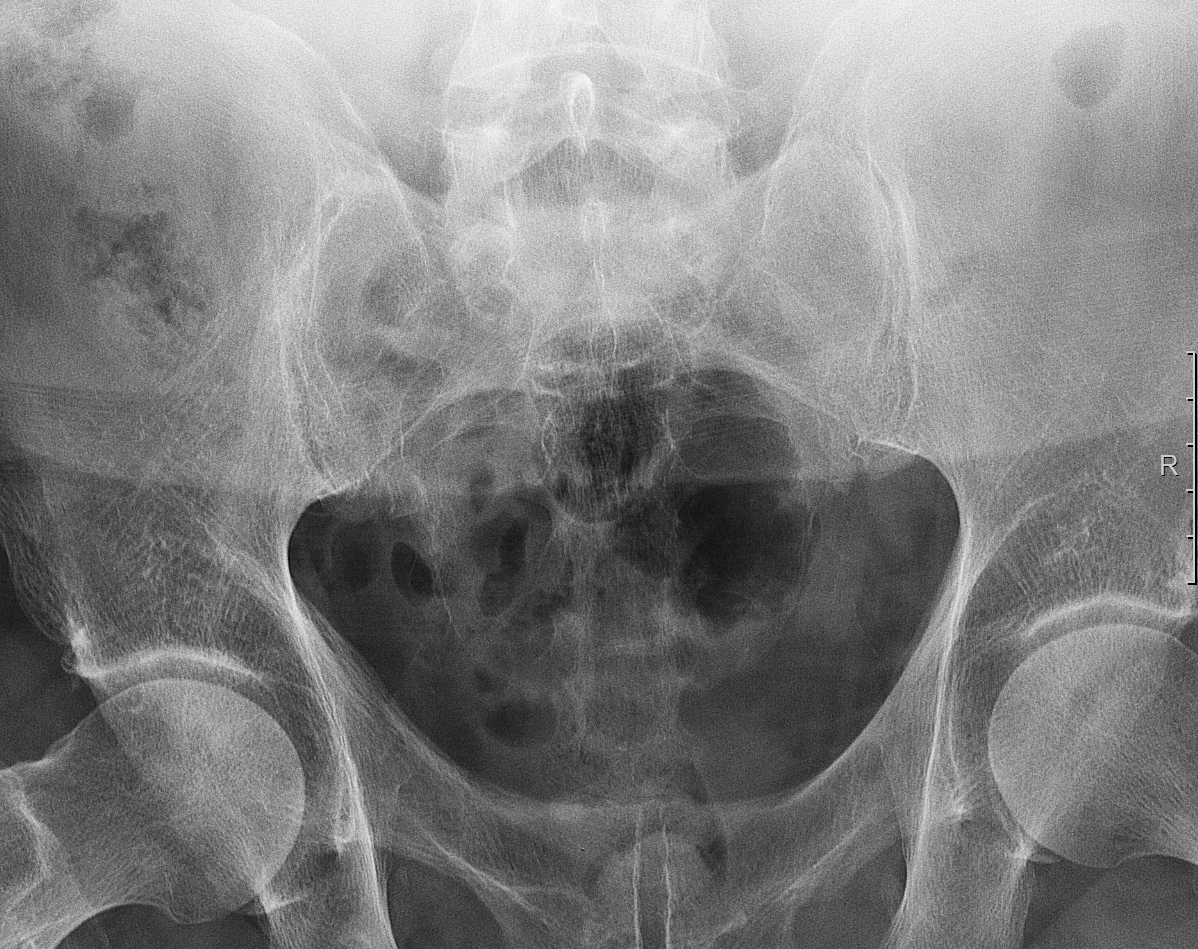

Рентгеновские снимки плат в высоком разрешении